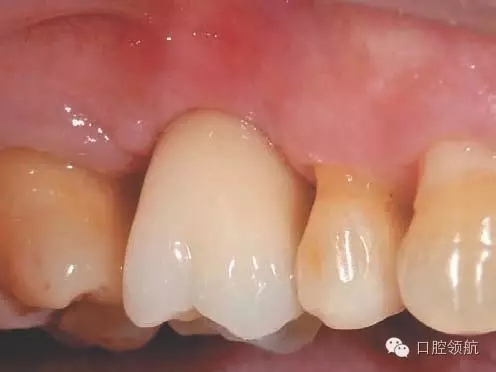

術(shù)后12周在獲得骨結(jié)合后,開始制作上部結(jié)構(gòu),術(shù)后16周戴入(圖8)。術(shù)后24周,CBCT影像顯示,種植體周圍有足夠的骨量(圖9)。

圖8 術(shù)后16周戴入上部修復(fù)體。

圖9 術(shù)后24周,CBCT影像顯示通過拔牙后早期植入,能夠進(jìn)行安全確實的上頜竇底提升術(shù)。